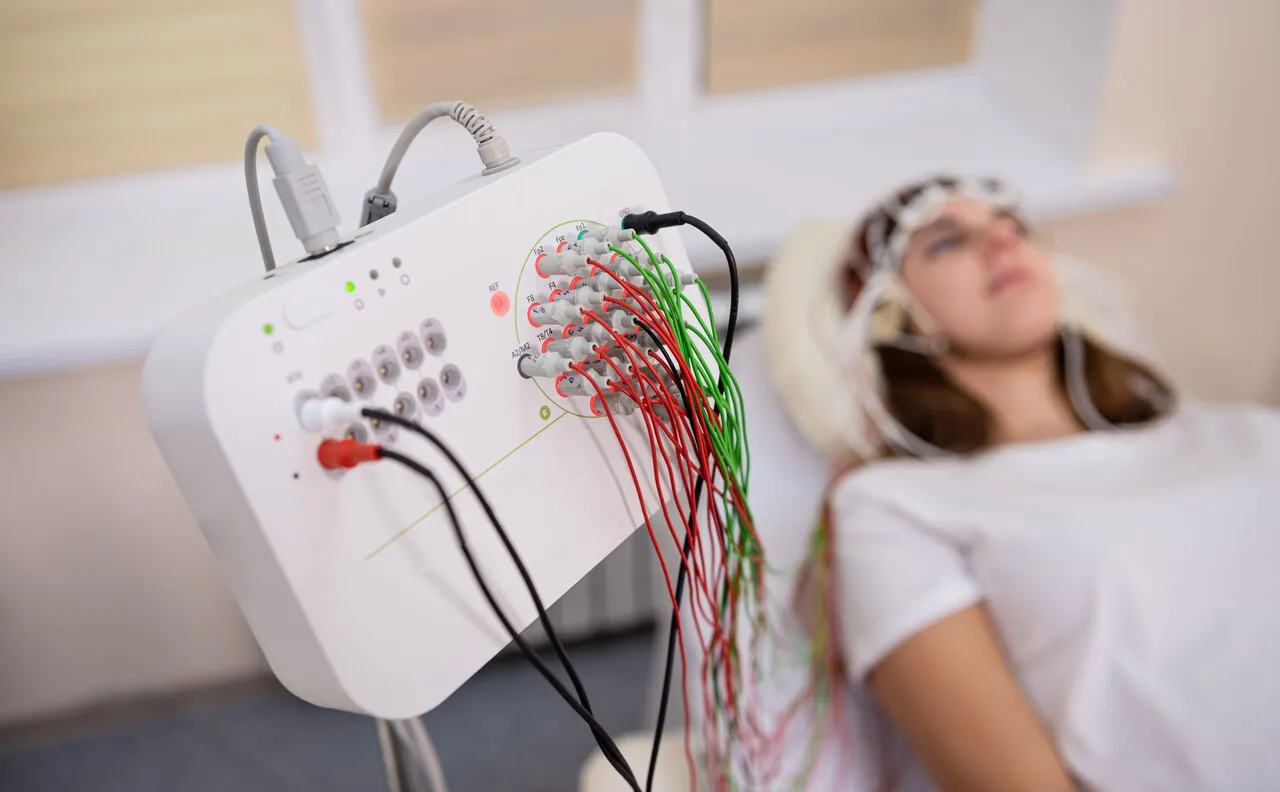

Registra a atividade elétrica do cérebro para auxiliar no diagnóstico de alterações neurológicas.

EEG mais detalhado que utiliza maior número de sensores para análise aprofundada da atividade cerebral.